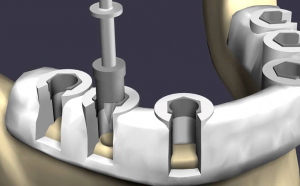

Одним из самых значимых достижений стоматологии в XX веке является имплантация зубов. Используя данную технологию, можно воссоздать естественный вид зубов. Это в свою очередь предотвращает атрофию костной ткани и деформацию десны. Процедура имплантации также позволяет вернуть полноценную жевательную функцию, не нанося при этом вреда другим зубам.

На противоположность мостовой конструкции, которая приводит к излишнему давлению и износу зубов. Кроме того, в отличие от других видов протезирования, импланты могут прослужить более 20-25 лет.

В нашем современном мире основным методом лечения зубов является имплантация.

В настоящее время при отсутствии большинства зубов на челюсти пациенту может быть предложено решение в виде процедуры all-on-4 («все на четырех») или all-on-6 («все на шести») соответственно. Оба метода являются практичными, надежными и достаточно доступными.

При использовании метода all-on-4 пациенту вживляются четыре импланта: два устанавливаются на место передних зубов и два на место жевательных. Благодаря применению высококачественных материалов и запатентованной технологии четыре импланта обладают достаточной прочностью для удержания конструкции, которая заменяет все зубы на челюсти. В случае метода all-on-6 процедура имплантации аналогична, только устанавливаются шесть имплантов вместо четырех.

Процесс all‑on‑4 или all‑on‑6 может быть затруднен из-за образования атрофии и уменьшения плотности кости, что делает невозможным вкручивание имплантатов. В любом случае, это не означает отсутствие альтернативы, такой как базальная имплантация, когда 8-12 зубных штифтов устанавливаются в кости с помощью прокола и вкручивания. Это позволяет равномерно распределить нагрузку на челюсть.

С современными навигационными технологиями установка базальных имплантатов становится практически безопасной процедурой в современных стоматологических клиниках.

Шаблон для навигационной имплантации

Перед проведением базальной имплантации, пациенту необходимо пройти компьютерную томографию челюсти. По результатам снимков строится трехмерная модель с точечными и угловыми координатами проколов в челюсти. Все вычисления выполняются компьютером при помощи специальной программы. В итоге создается навигационная модель — уникальный шаблон с отверстиями. Во время операции стоматолог устанавливает шаблон на челюсть и вставляет сверло в отверстие, пока оно не заблокируется.

Три варианта имплантации, которые были описаны выше, относятся к методу немедленной нагрузки. После установки штифтов импланта производится установка временного протеза через 2-3 дня. Этот протез носится до полного срастания титановых стержней и дает пациенту возможность жевать и полноценно жить. После полной реабилитации устанавливается постоянная конструкция.

Однако, импланты имеют и некоторые недостатки, такие как медицинские противопоказания, высокая стоимость по сравнению с традиционными методами лечения, а также необходимость хирургического вмешательства, включая разрез десны, вживление «ножки» импланта и, при необходимости, наращивание костной ткани.